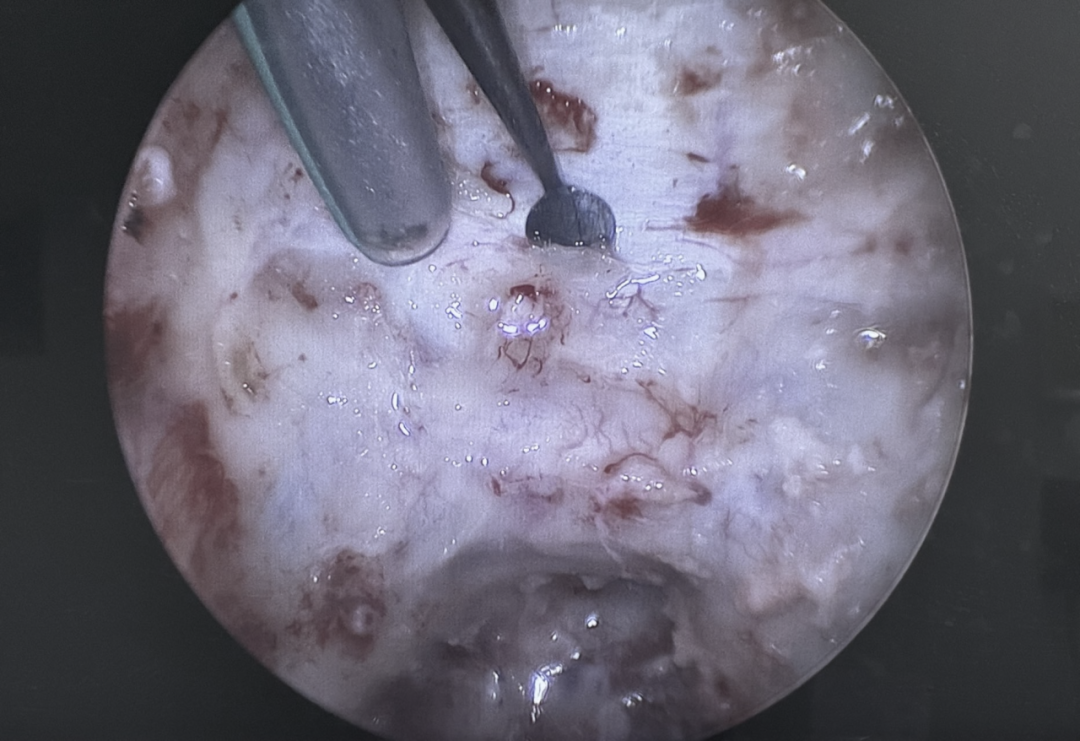

日本医疗团队在术中给我最大的感受是极具耐心和精细操作,尤其内镜手术颇有特色,每一位医师都能掌握,手术时间有时虽然很长,但对解剖结构清晰把握能够让我们紧跟术者的步伐、充分体会手术的真正精髓。

科室对于功能区病灶能够精准处理,研修期间我目睹了多例清醒手术,包括癫痫灶的切除、功能区肿瘤的切除等,通过术中唤醒、持续电生理监测,能够最大程度的保存患者的语言、运动功能,而大阪公立大学附属病院也已取得多年的清醒手术资质,积累了多年的手术经验。

这是一台脑动脉瘤手术,通过术前影像、术中精细梳理,很快找到了动脉瘤,再通过多次的试夹闭,保留了穿支血管。